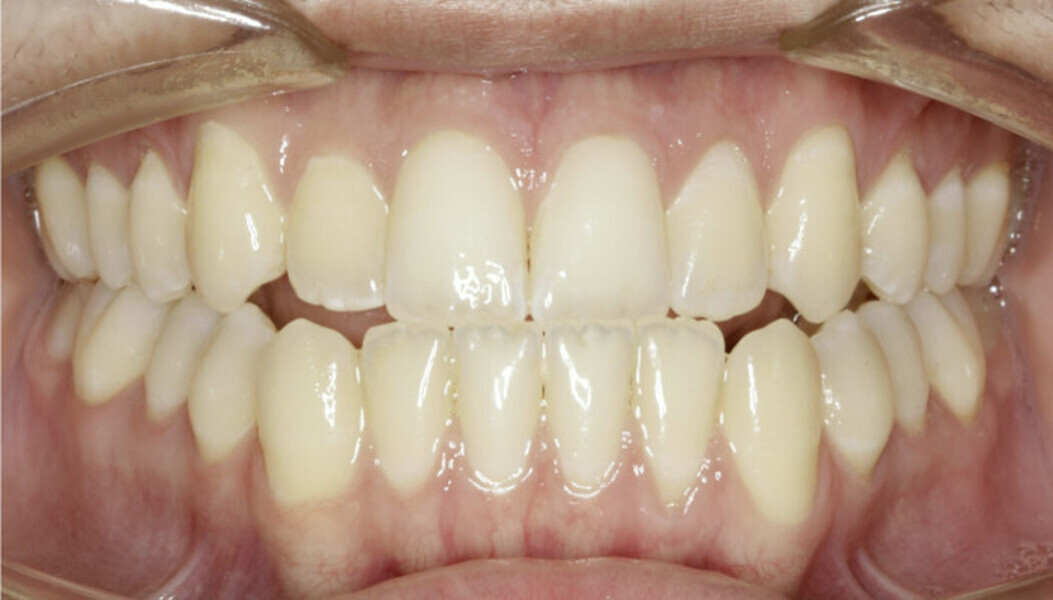

New Age orthodontics and orthopaedics with temporary anchorage devices